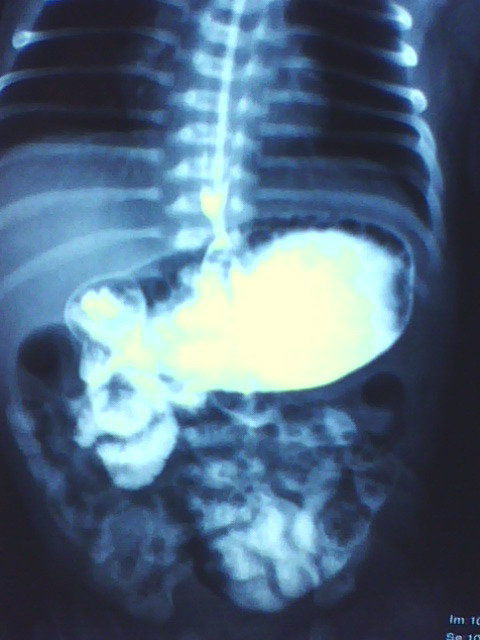

以下是引用拾荒者在2009-10-14 20:41:00的发言:[br]要查的话也应该做钡灌肠,看有否巨结肠及乙状结肠冗长症等;做上消化道钡餐想看什么?5天的小儿肠腔胀气是正常的。